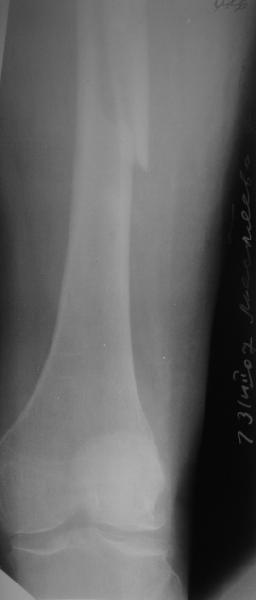

На прошлой неделе пациентке 74 лет, было выполнено цементное эндопротезирование тазобедренного сустава по поводу перелома шейки бедра.Активизирована на следующий день, ходила с костылями, нагрузка полная.Дело близилось к выписке, когда она, подскользнувшись упала в палате и получила то, что  видите на снимках.Что бы Вы стали делать в подобной ситуации? Заранее спасибо.